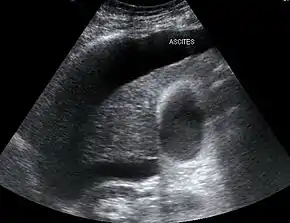

Both types of hepatorenal syndrome share three major components: altered liver function, abnormalities in circulation, and kidney failure. As these phenomena may not necessarily produce symptoms until late in their course, individuals with hepatorenal syndrome are typically diagnosed with the condition on the basis of altered laboratory tests. Most people who develop HRS have cirrhosis, and may have signs and symptoms of the same, which can include jaundice, altered mental status, evidence of decreased nutrition, and the presence of ascites.[2] Specifically, the production of ascites that is resistant to the use of diuretic medications is characteristic of type 2 HRS. Oliguria, which is a decrease in urine volume, may occur as a consequence of kidney failure; however, some individuals with HRS continue to produce a normal amount of urine.[3] As these signs and symptoms may not necessarily occur in HRS, they are not included in the major and minor criteria for making a diagnosis of this condition; instead HRS is diagnosed in an individual at risk for the condition on the basis of the results of laboratory tests, and the exclusion of other causes.[3]

The major criteria include liver disease with portal hypertension; kidney failure; the absence of shock, infection, recent treatment with medications that affect the function of the kidney (nephrotoxins), and fluid losses; the absence of sustained improvement in kidney function despite treatment with 1.5 litres of intravenous normal saline; the absence of proteinuria (protein in the urine); and, the absence of kidney disease or obstruction of kidney outflow as seen on ultrasound.[3]

Individuals with ascites that have become infected spontaneously (termed spontaneous bacterial peritonitis or SBP) are at an especially high risk for the development of HRS.[2] In individuals with SBP, one randomized controlled trial found that the administration of intravenous albumin on the day of admission and on the third day in hospital reduced both the rate of kidney insufficiency and the mortality rate.[22]